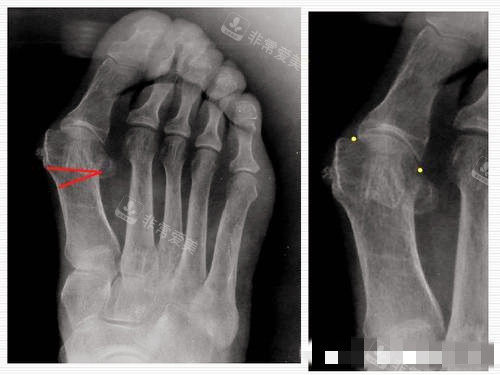

这种手术的优点非常明显,它的创伤小,术后改善快,而且能够有效地矫正脚型。通过详细的资料查阅,我了解到小创口截骨矫正手术是通过微小的切口,将畸形的骨骼进行截断和重新固定,从而达到矫正大脚骨的目的。与传统的手术相比,它减少了对周围组织的损伤,降低了术后感染的风险,同时也缩短了改善时间。

怀着紧张又期待的心情,我来到了韩国的整形医院。医院的环境非常舒适,工作人员也都非常热情和正规。在面诊时,医生仔细地检查了我的脚部情况,用正规的仪器进行了详细的测量和分析。

医生根据我的具体情况,制定了个性化的手术方案。他耐心地向我解释了手术的过程、风险和术后注意事项,让我对手术有了更多方面的了解。我也向医生提出了自己的疑问和担忧,医生都一一进行了解答,让我心里踏实了许多。